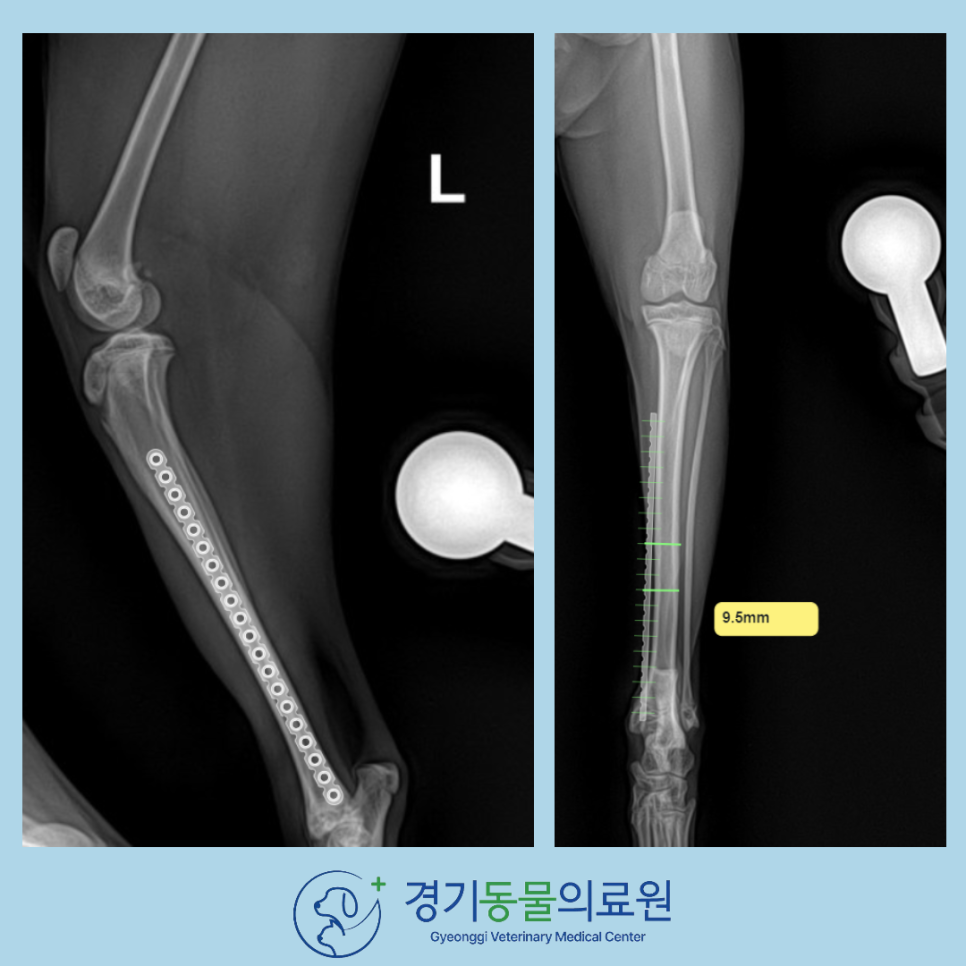

이에 따라, plate and screw를 통한 고양이 경골 골절 수술을 진행하였습니다.

고양이 경골 골절 수술 전 계획을 통해 뼈의 크기와 가장 맞는 임플란트 선택을 위해, 고양이이 정형외과 수술용 컴퓨터 프로그램을 사용하고 있습니다.

수술 과정에서는

✔ 골편 정렬 복원

✔ 다리 길이 및 축 정렬 확인

✔ 안정적인 임플란트 배치

를 반복적으로 확인하여 정상적인 체중 부하가 가능하도록 정밀 교정을 진행했습니다.